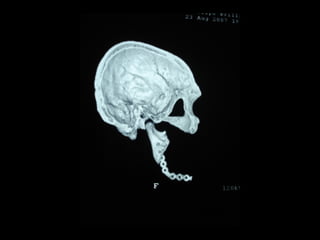

Diagnóstico por Imágenes

• Rx Extraorales: Teleradiografías y

Ortopantomografías

• Rx intraorales: Oclusales y Rx. Periapicales.

• Fundamentalmente Tomografías

Diagnóstico por Imágenes •Rx Extraorales: Teleradiografías y Ortopantomografías • Rx intraorales: Oclusales y Rx. Periapicales. • Fundamentalmente Tomografías